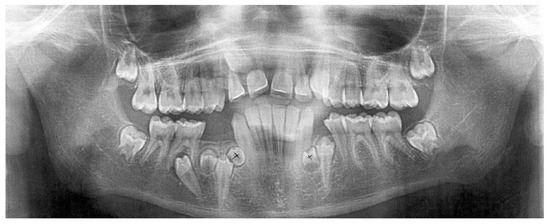

Tooth Migration in a Female Patient with Hyperdontia: 11-Year Follow-Up Case Report

2. Case Report